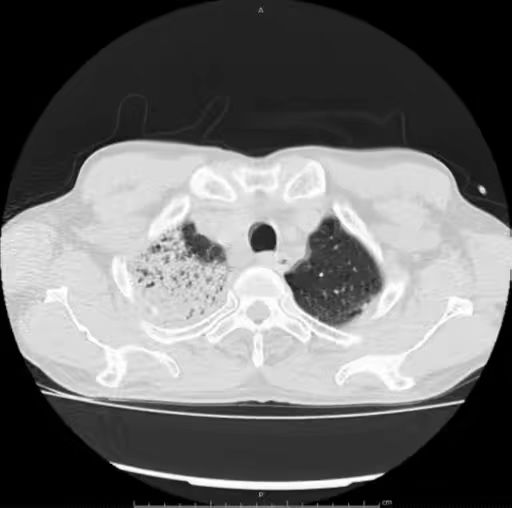

2.  右肺上叶尖段是否占据整个层面?

肺炎链球菌肺炎多为肺泡性肺炎,少数血播肺炎链球菌肺炎好发于老年人及免疫力低下人群,PCT 明显增高。影像上,早期在血管炎的基础上仍能见到按肺小叶充填及闲置的表现(肺泡性肺炎的表现),而大片实变影已不能分辨是否为血管炎(病灶边缘磨玻璃仍可看出血管炎),在肺尖段不会占据整个层面(与铜绿假单胞菌肺炎不同),而在下肺往往表现为齐头并进的特点,分布上多上肺优势。